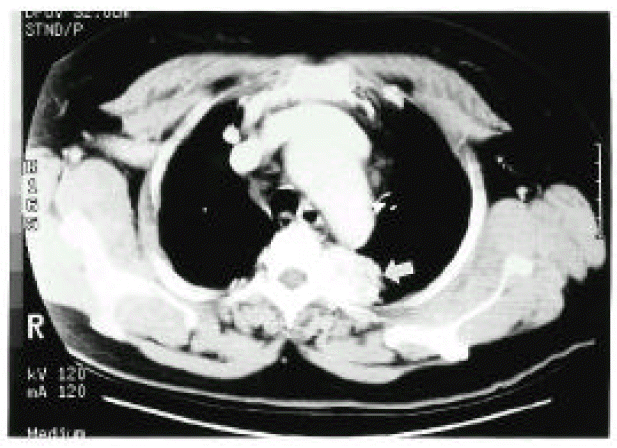

Figure 1.

The CT scan of the thorax at aortic arch level showed a 4×3×3 cm-sized, well-defined mass in the posterior mediastinum. The mass showed high density with good contrast enhancement (arrow).